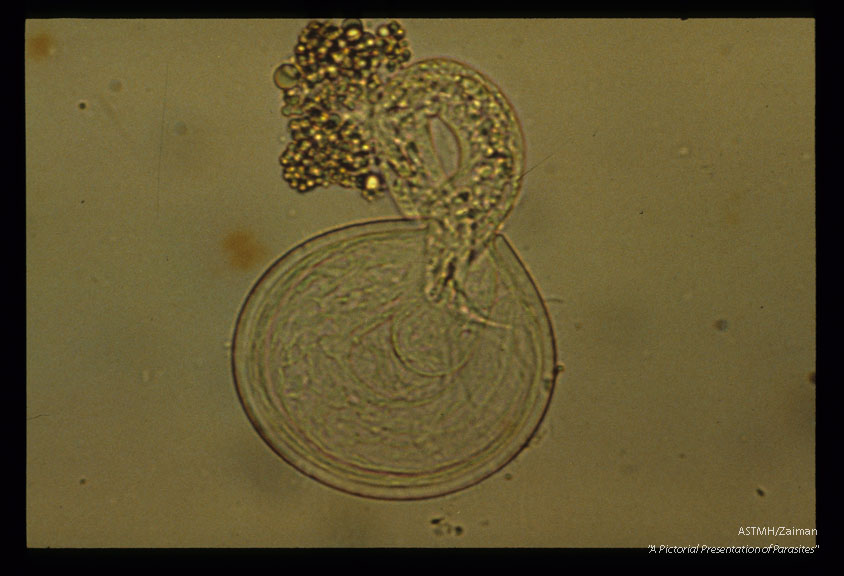

Development and hatching of larva.

Ascaris

Description: Development and hatching of larva.